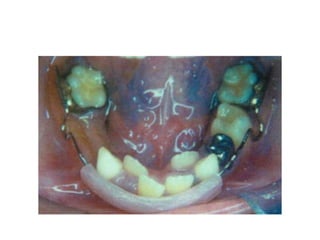

Severe Crowding:

• crowding is so severe (>10mm/arch)

• in the mixed dentition arch expansion is not

feasible

• serial extraction is necessary

Sequence of extractions

• Bunon (1743) – primary canines, first primary

molars and first premolars

• Dewels method – C D 4

• Tweeds method – D 4 C

• Nance method – D4 C

• Most satisfactory order